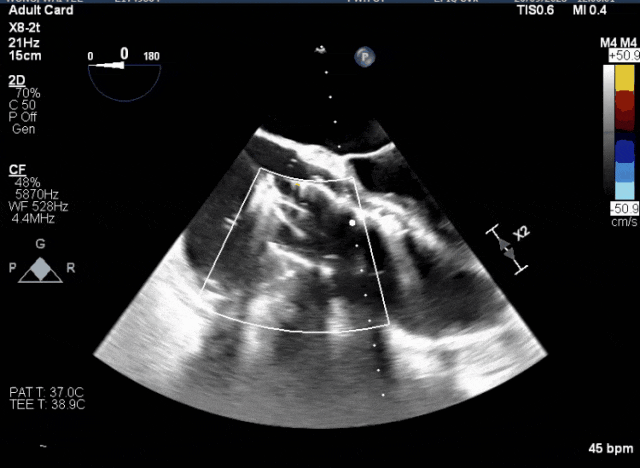

術(shù)中TEE觀察夾持件的位置

術(shù)后超聲評(píng)估瓣膜穩(wěn)定性良好,無瓣周漏